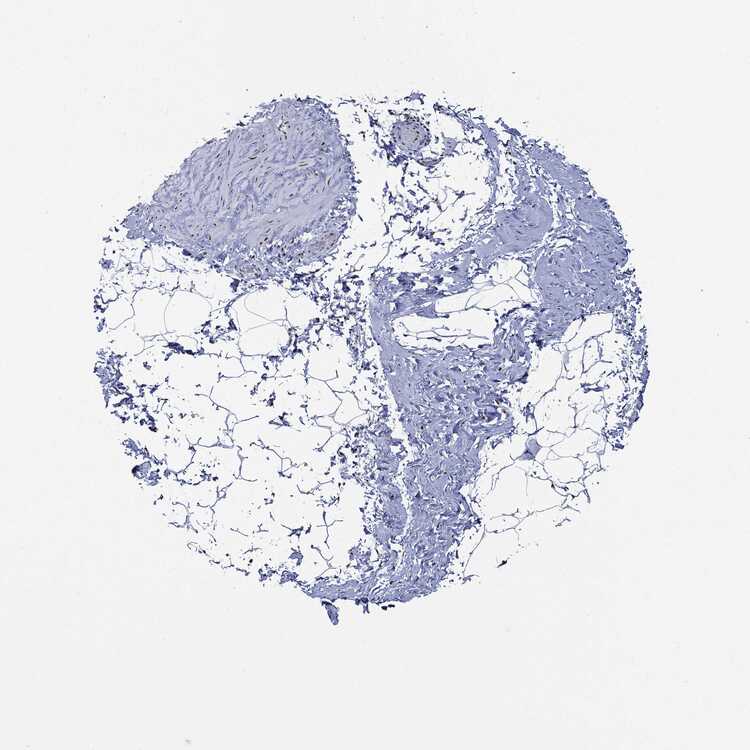

SOFT TISSUE 1 - Antibody stainingi

Antibody staining in the annotated cell types in the current human tissue is reported as not detected, low, medium, or high, based on conventional immunohistochemistry profiling in selected tissues. This score is based on the combination of the staining intensity and fraction of stained cells.

Each image is clickable and will lead to virtual microscopy that enables deeper exploration of all samples and also displays staining intensity scores, fraction scores and subcellular localization as well as patient and tissue information for each sample.

Antibody HPA030521Antibody HPA030522Antibody HPA030523Antibody CAB000148Antibody CAB080240Antibody CAB080241Antibody CAB080242

Chondrocytes Medium-Not detected--Not detectedNot detected

Fibroblasts Not detectedMediumNot detectedNot detectedNot detectedMediumMedium

Peripheral nerve Not detected-----Not detected